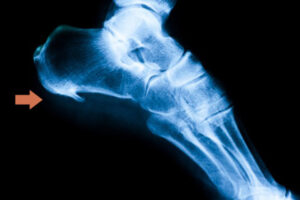

Lo sperone calcaneare è una crescita ossea a forma triangolare o di lancia che si verifica quando la fascia plantare (il tessuto elastico che collega il tallone alla base delle dita del piede) è sottoposta a eccessiva trazione e sovraccarico, generando micro-rotture nella sua inserzione. Questa parte si calcifica formando una sorta di “osso” che provoca un dolore acuto nel tallone, simile a una sensazione di puntura.